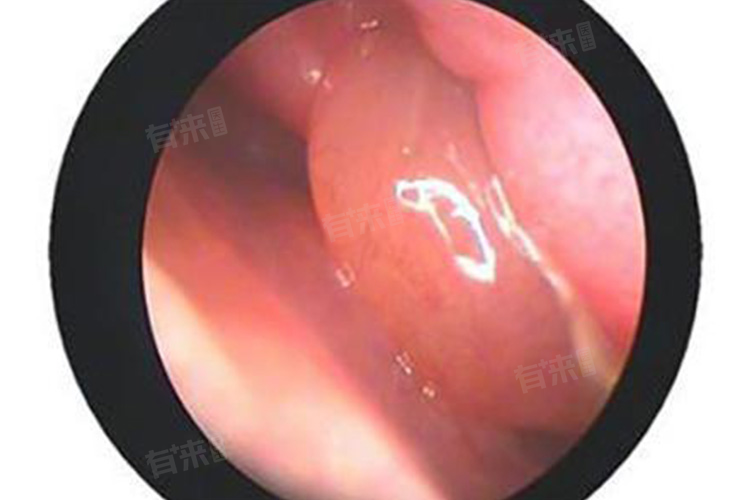

- 耳鼻喉科:若孩子鼻甲肿大伴有明显鼻塞、流涕、头痛等症状,耳鼻喉科是关键选择。该科室医生专注于耳鼻喉区域疾病,借助鼻内镜等专业设备,能清晰观察鼻甲形态、大小,查看鼻黏膜是否充血、有无分泌物潴留,精准判断鼻甲肿大程度与病因,如是否存在慢性鼻炎、鼻窦炎等,进而给出针对性治疗建议。